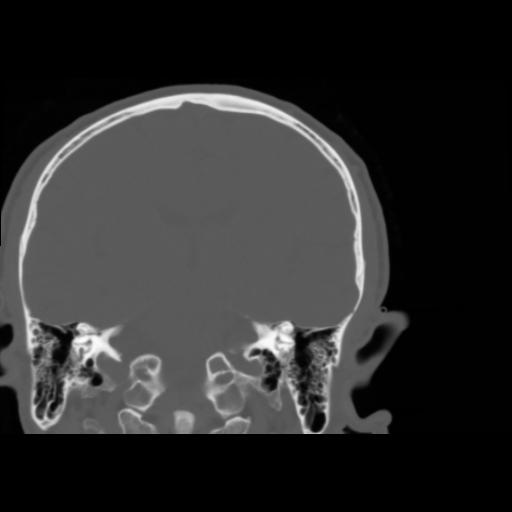

5 CEREBRO,,Coronal,3.000,CEREBRO,Coronal,